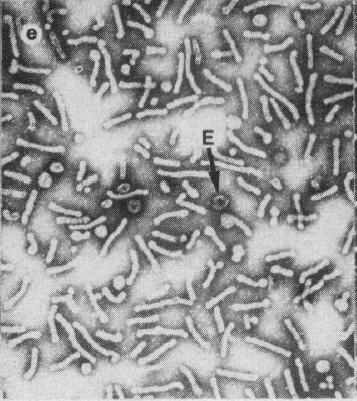

Alexander Fleming(弗莱明)发现了盘尼西林,就是著名的青霉素。这可能是历史上最偶然的科学发现。在研究各型葡萄球菌时,弗莱明将一些培养皿置于实验台上以用于日后观察。几天后,他发现培养物被霉菌孢子所污染,但惊奇地发现,在霉菌孢子生长的区域,葡萄球菌被击退了。尽管弗拉明已经发现了青霉素,但是正式的临床应用却在十年以后,因为制造青霉素很难,并且青霉素对其它细菌性感染的治疗作用还没有被认可。1940年代,德国开始侵犯欧洲,牛津的一群科学家的工作使大规模生产青霉素称为可能,并且最终认识到了青霉素的强大疗效。